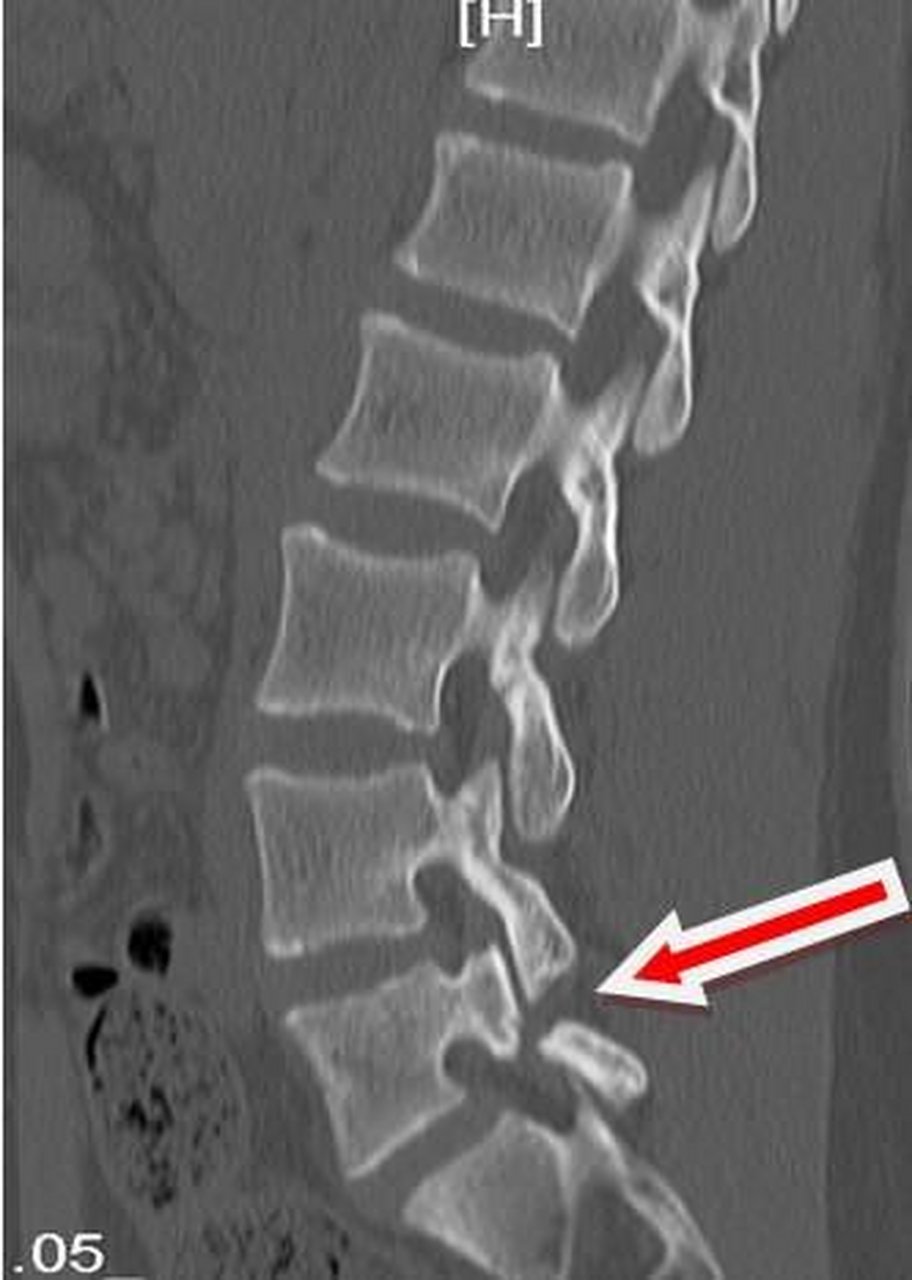

腰椎峡部裂(lumbar spondylolysis)

图片尺寸598x715